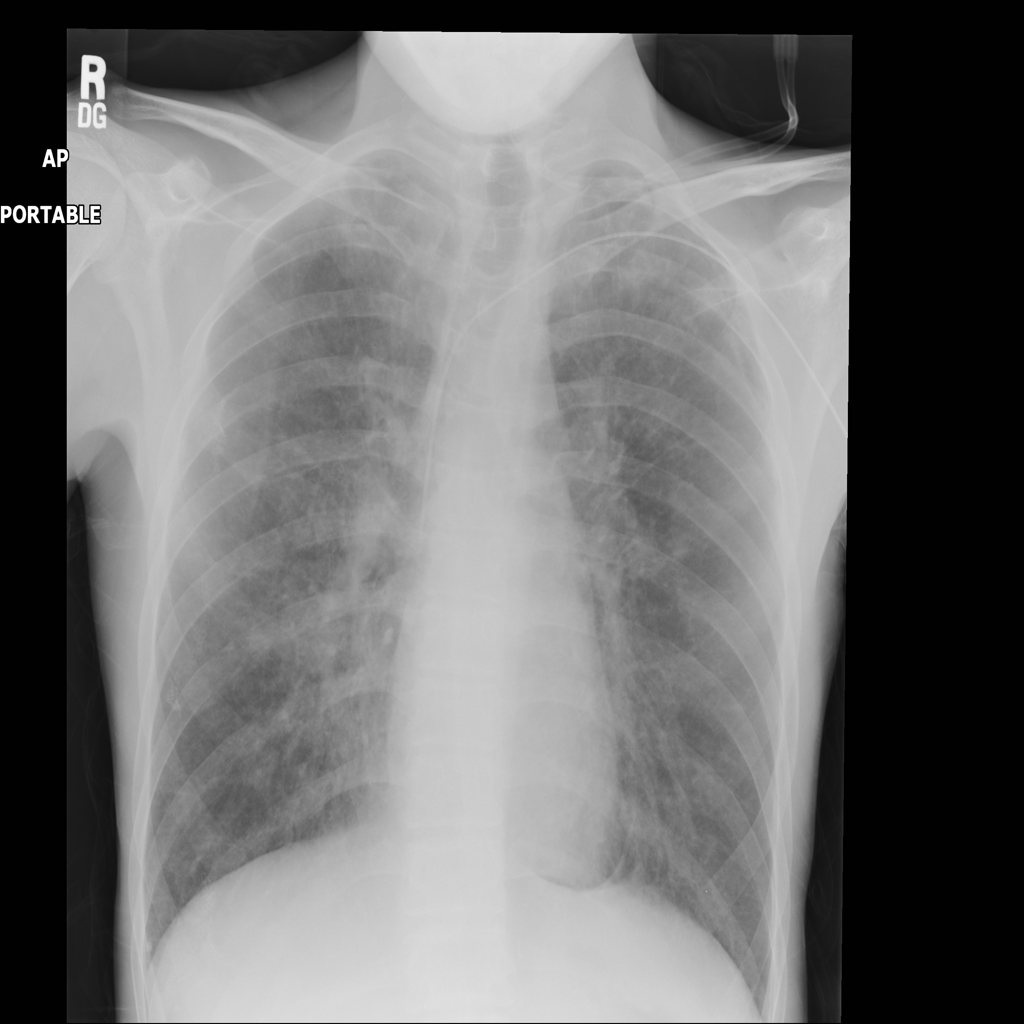

Showing up to 90 reference images for Pneumothorax.

PAT-4639 · IMG-012Pneumothorax

PAT-4639 · IMG-012

AP